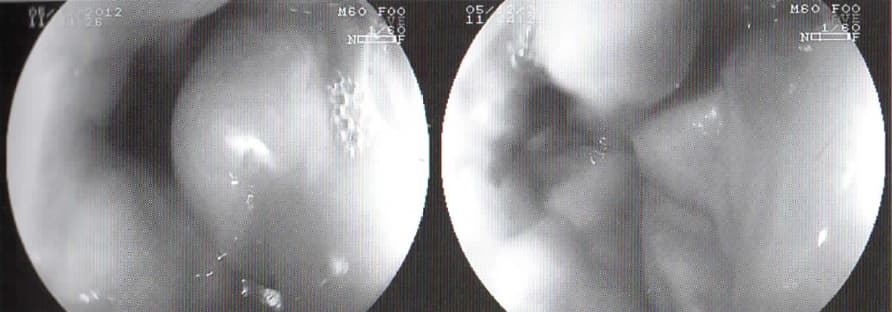

Křečové žíly jícnu, endoskopický obraz (vlastní pozorování)

Jícnové varixy s mnohočetnými defekty sliznice po profuzním krvácení, pitevní materiál (vlastní pozorování)